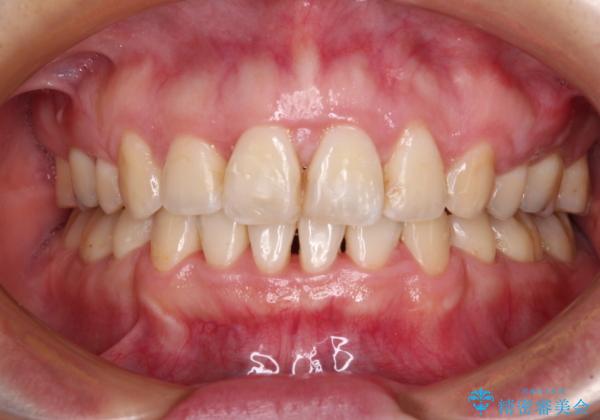

- 出っ歯と口の閉じにくさ、デコボコを気にして来院された患者様です。

口元の突出感を改善するため、上下左右第一小臼歯4本の抜歯を行い、ワイヤー装置による矯正治療を行うこととしました。